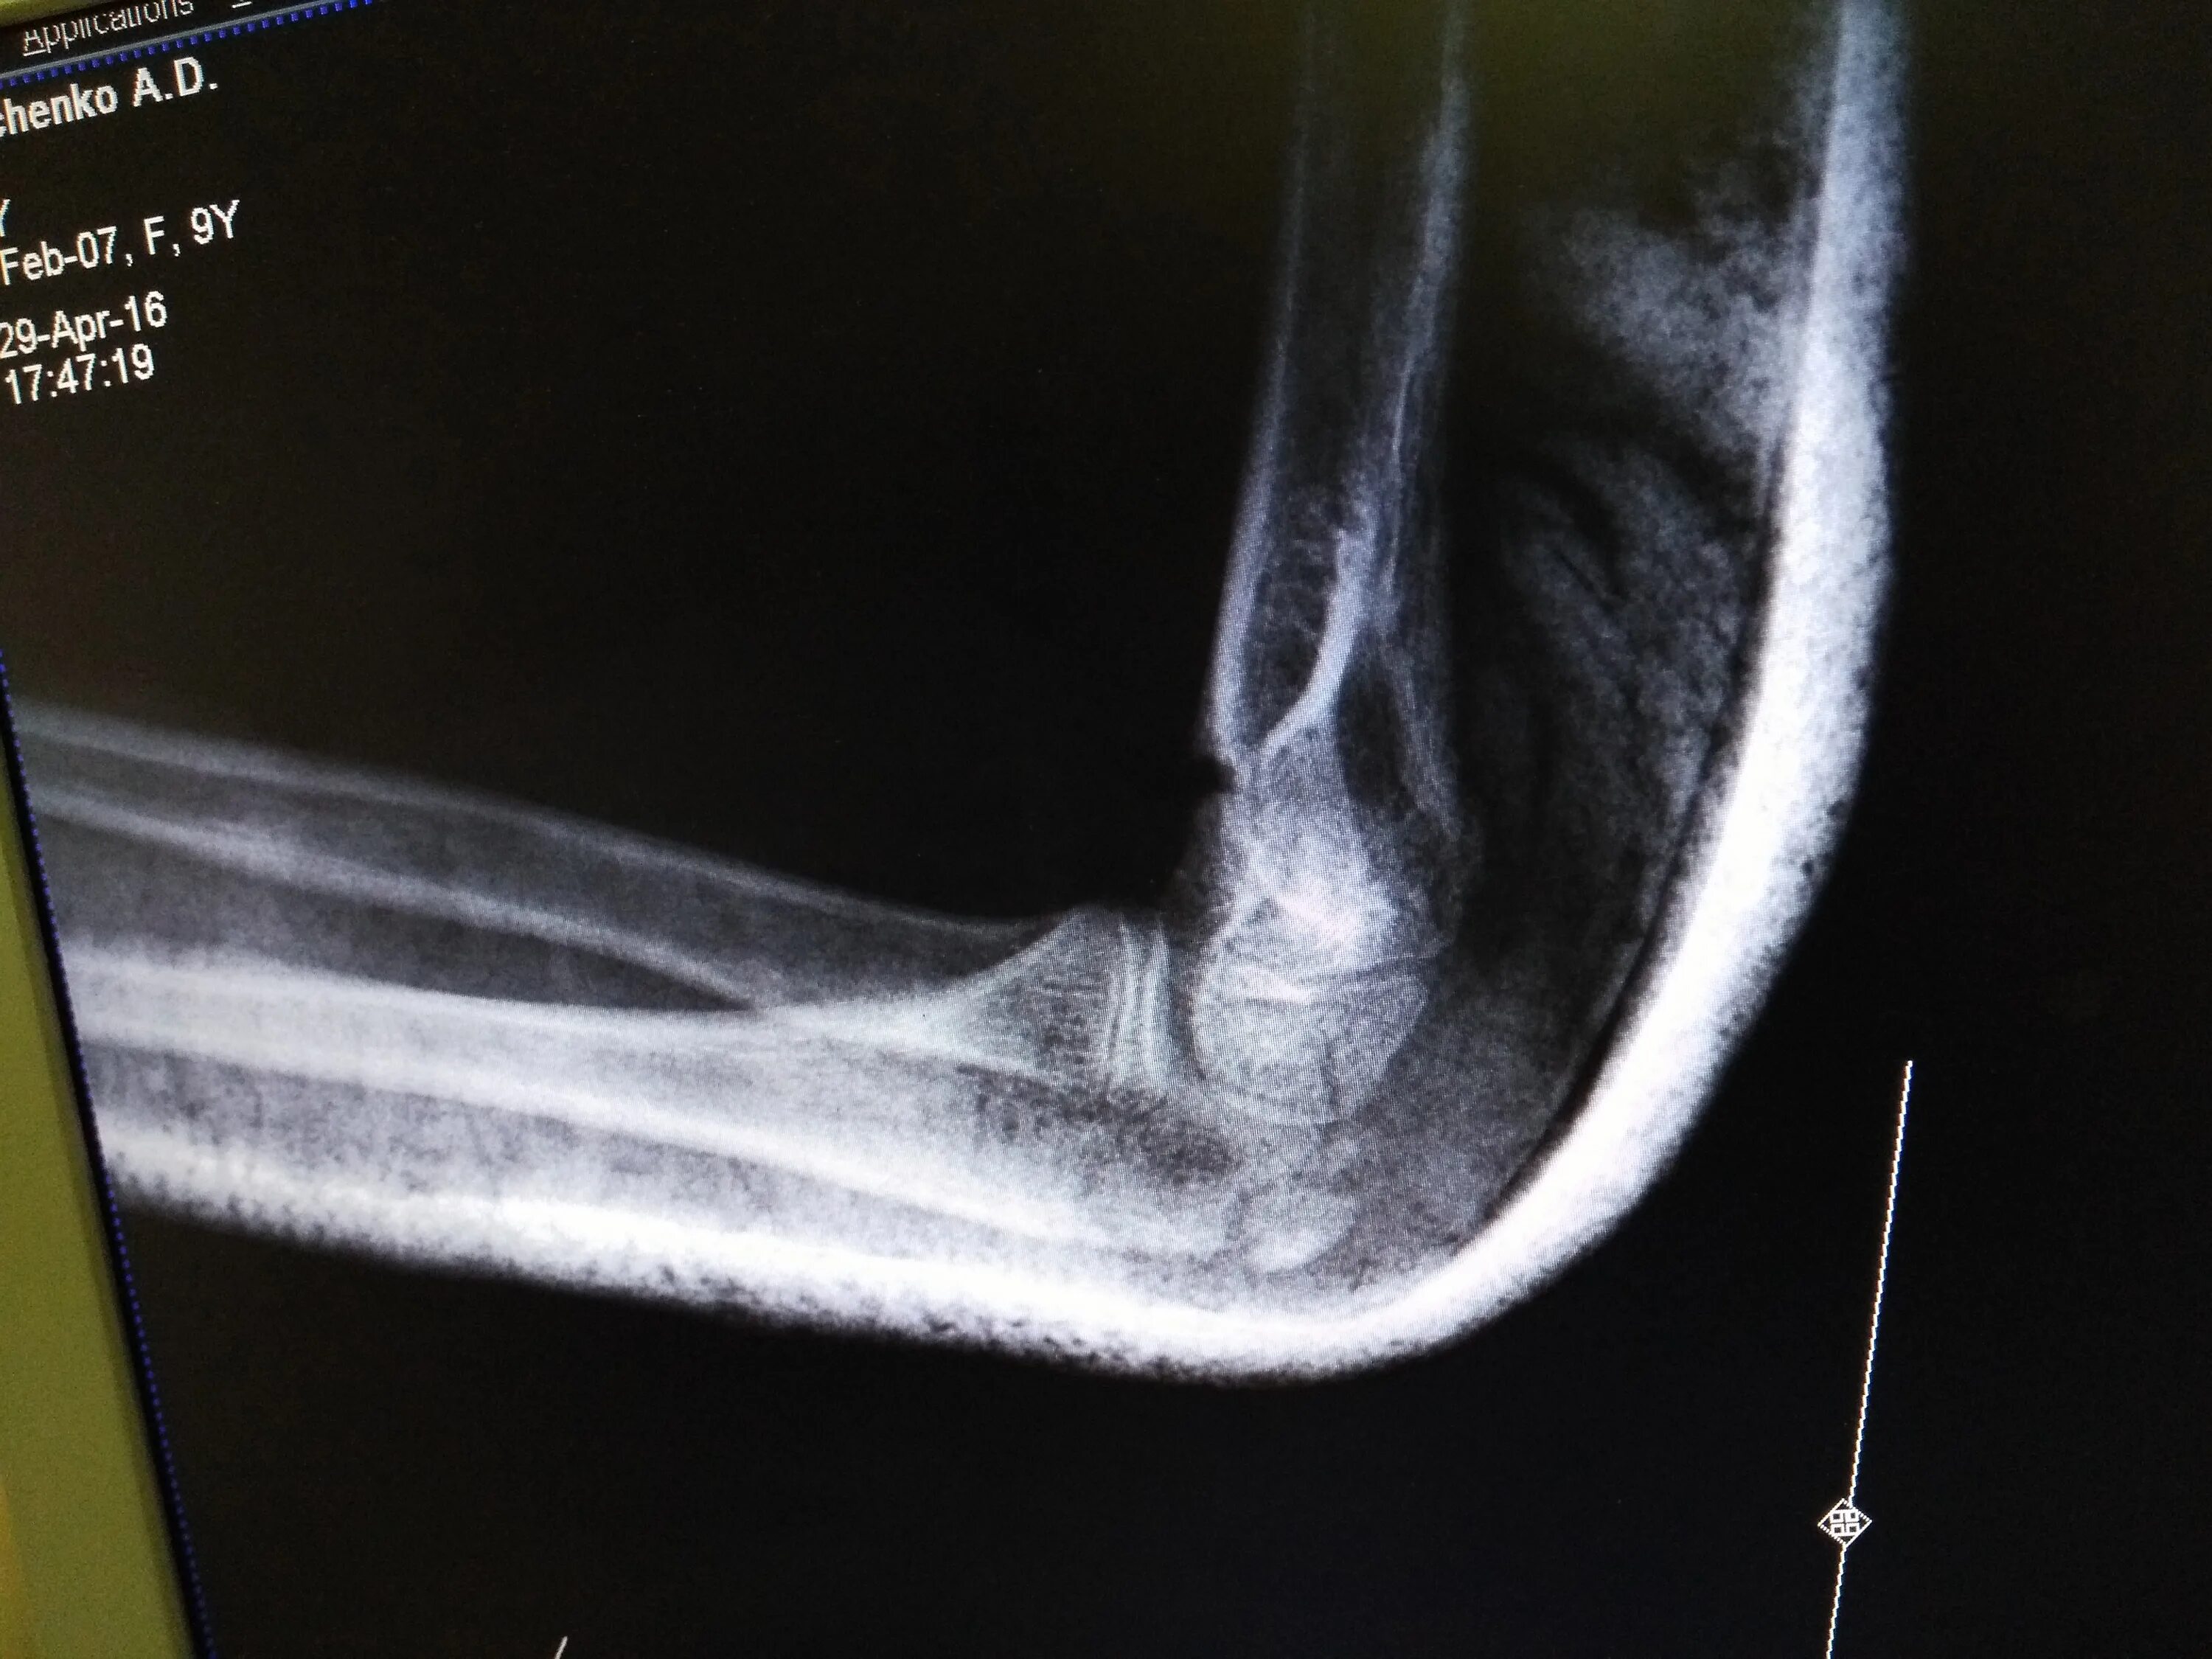

Латеральный эпикондилит мкб 10